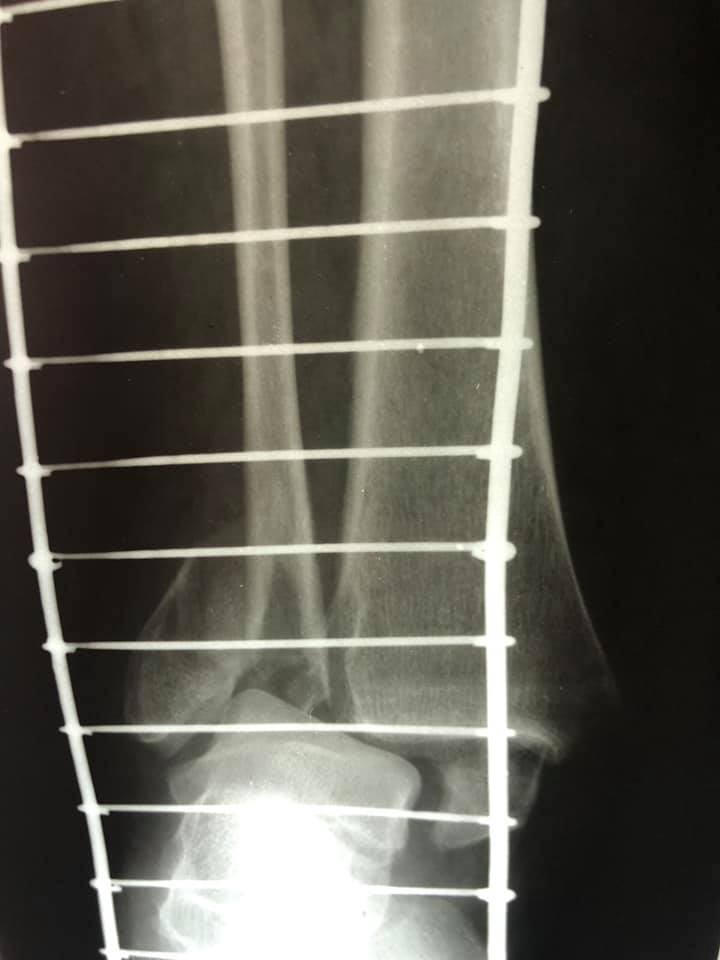

Завдяки вчасному зверненню та професіоналізму лікаря-ортопеда-травматолога, жінку вдалося врятувати. В ургентному порядку жінку доставили в КНП «НЦМЛ». Після огляду лікар встановив діагноз: відламковий перелом кісточок гомілки з вивихом стопи.

Пацієнтці виконали відкриту репозицію уламків з внутрішньою фіксацією. Операція пройшла успішно.